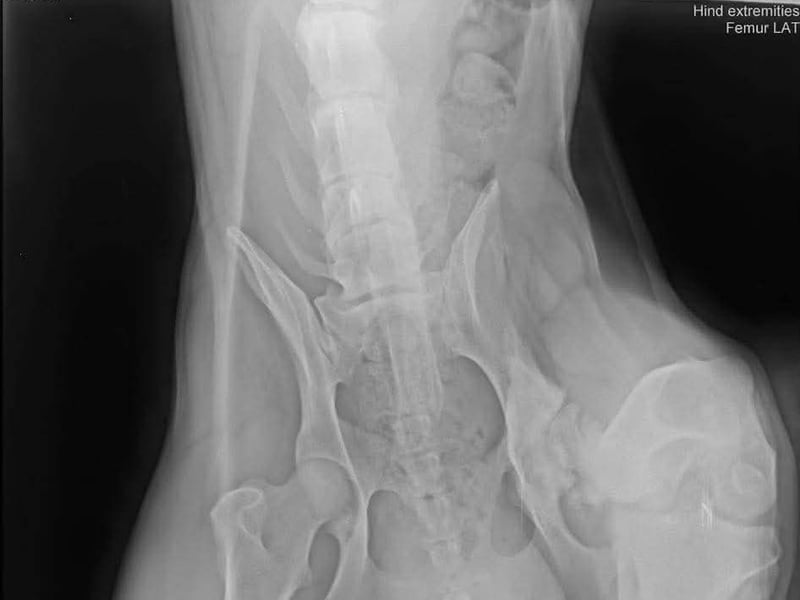

Bemerkungen: Marli hatte eine OP am Knie

Marli kam aus einer Romasiedlung. Er konnte nicht richtig laufen. Der Tierarzt stellte eine alte Knieverletzung fest die dann umgehend operiert wurde. Alles ist sehr gut verheilt und heute genießt Marli sein neues Leben.